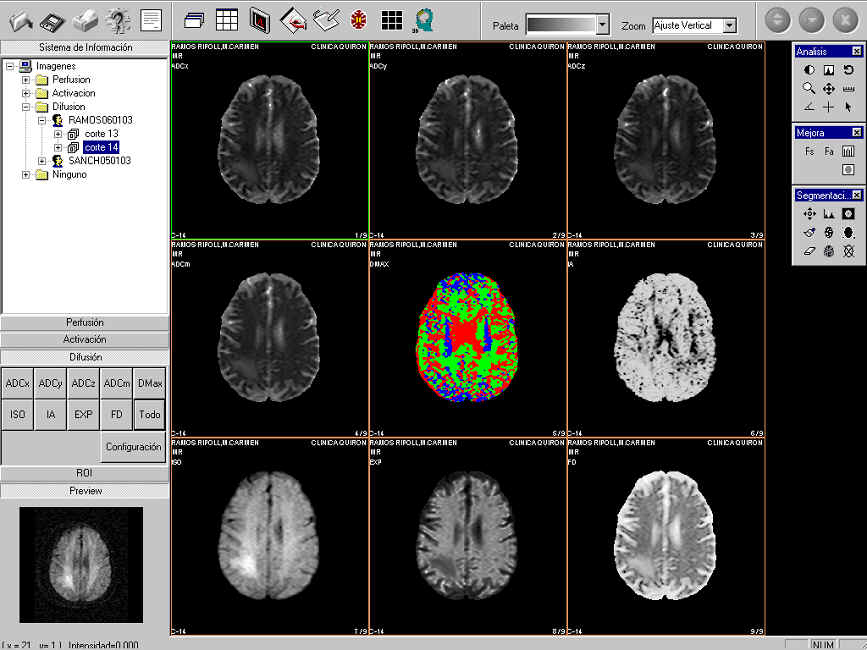

Fig 3. Captura del programa mostrando algunos mapas de disfusión.

Difusión

Las imágenes potenciadas en difusión(DWI) son una clase de imágenes de RM que son sensibles al movimiento de las moléculas de agua en cada uno de los tres ejes(x,y,z). A partir de estas imágenes podemos cuantificar la difusión aparente del agua cerebral(decimos aparente ya que el movimiento del agua cerebral tambien está influido por la perfusión).

Los mapas que podemos calcular son los siguientes: ADCx(Coeficiente de difusión Aparente en la dirección de fase) , ADCy(Coeficiente de difusión Aparente en la dirección de módulo) , ADCz(Coeficiente de difusión Aparente en la dirección de corte) , ADCm(Coeficiente de difusión Aparente medio) , IA( Indice de Anisotropía), ISO(Imagen de difusión Isotrópica), MD(Máxima difusión), EXP(Difusión exponencial) y FD(Factor de difusión) (Fig 3.).